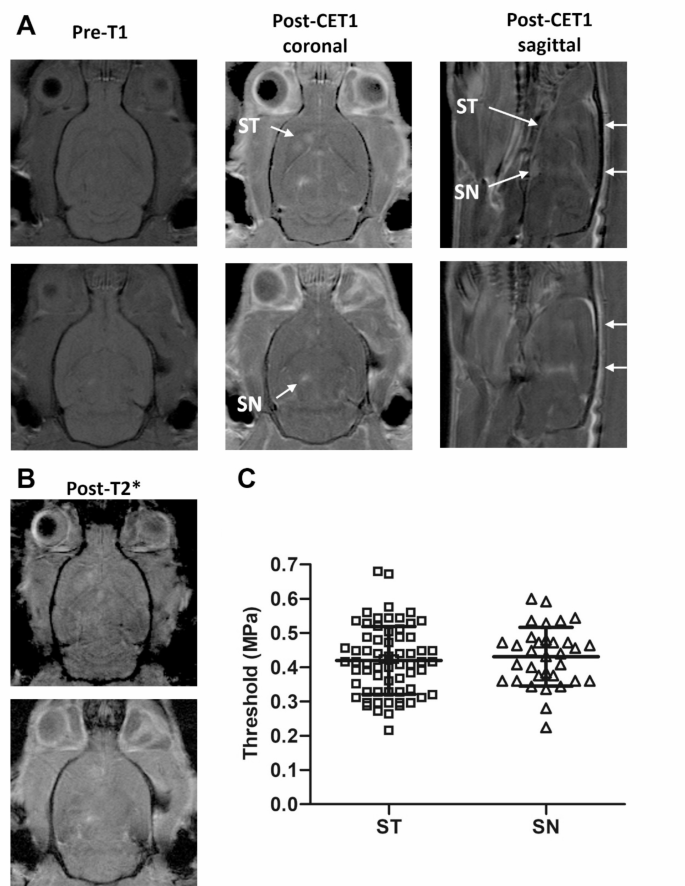

The goal of this experiment was to evaluate the efficacy of MRgFUS in enhancing BBB permeability in targeted brain regions, which is a critical step for subsequent MSC delivery in the Parkinson’s disease rat model. A schematic of the MRgFUS setup is depicted in Fig. 1. In brief, T2-weighted MR images were taken to precisely target the regions in the ST and SN in the lesioned hemisphere of the PD rats. 10 bursts at 0.128 MPa without microbubbles were used to capture the baseline emissions, followed by an intravenous injection of microbubbles. Upon detection of the acoustic threshold, the MSCs were injected immediately via the tail vein. The representative BBB permeability enhancement is shown in Fig. 2A, indicating that the enhancement was achieved in both the ST and SN. In addition, post-treatment T2* images (Fig. 2B) demonstrated no detectable hypo-intense signal in the targeted regions, which indicated no acute hemorrhage occurred due to the FUS sonication. Figure 2C shows the BBB permeability enhancement threshold for the ST (0.42 ± 0.10 MPa) and the SN (0.4 ± 0.09 MPa). No significant difference in the threshold was found between these two regions (p = 0.6).

Representative blood-brain barrier (BBB) permeability modulation in Parkinson’s disease rats after Magnetic resonance imaging-guided focused ultrasound. (A) T1-weighted images post-treatment demonstrated the BBB permeability enhancement in the striatum (ST) and substantia nigra (SN) in both coronal and sagittal views, compared to pre-treatment. (B) No obvious hypo-intense signal was found in the sonicated regions in the post-sonication T2* images. (C) The BBB permeability enhancement thresholds in ST and SN using the acoustic controller.